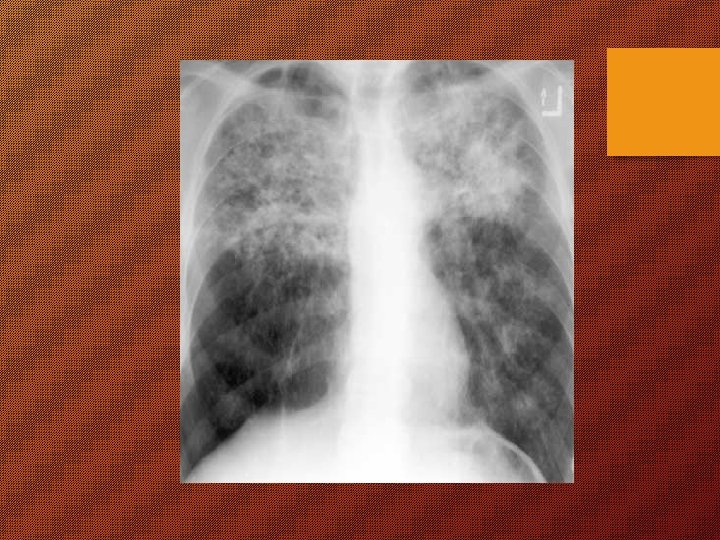

KAPAN DIPIKIRKAN SESEORANG MENDERITA TB ? Ø “batuk berdahak terus menerus 2 minggu atau lebih” (3 B) batuk darah atau dahak bercampur darah Ø Ø lemas, nyeri dada nafsu makan kurang Ø Ø Ø sesak nafas BB menurun demam meriang > 1 bln berkeringat malam tanpa kegiatan fisik.

Suspek TB (tersangka TB) “batuk berdahak terus menerus 2 minggu atau lebih”

Pemeriksaan Pasien TB Ø harus diperiksa dahaknya dgn menggunakan mikroskop Ø pemeriksaan lain sebagai tambahan. Pemeriksaan dahak untuk : - diagnosis - menilai kemajuan pengobatan - menentukan potensi penularan (positif 1 - 2 - 3).

Bekas pasien TB Bila telah dinyatakan sembuh, mungkin masih ada gejala batuk, sesak nafas dsb gejala sisa lantaran kerusakan paru atau penyebab lain Kadang-kadang cukup mengganggu periksakan diri ke puskesmas, BP 4, RS